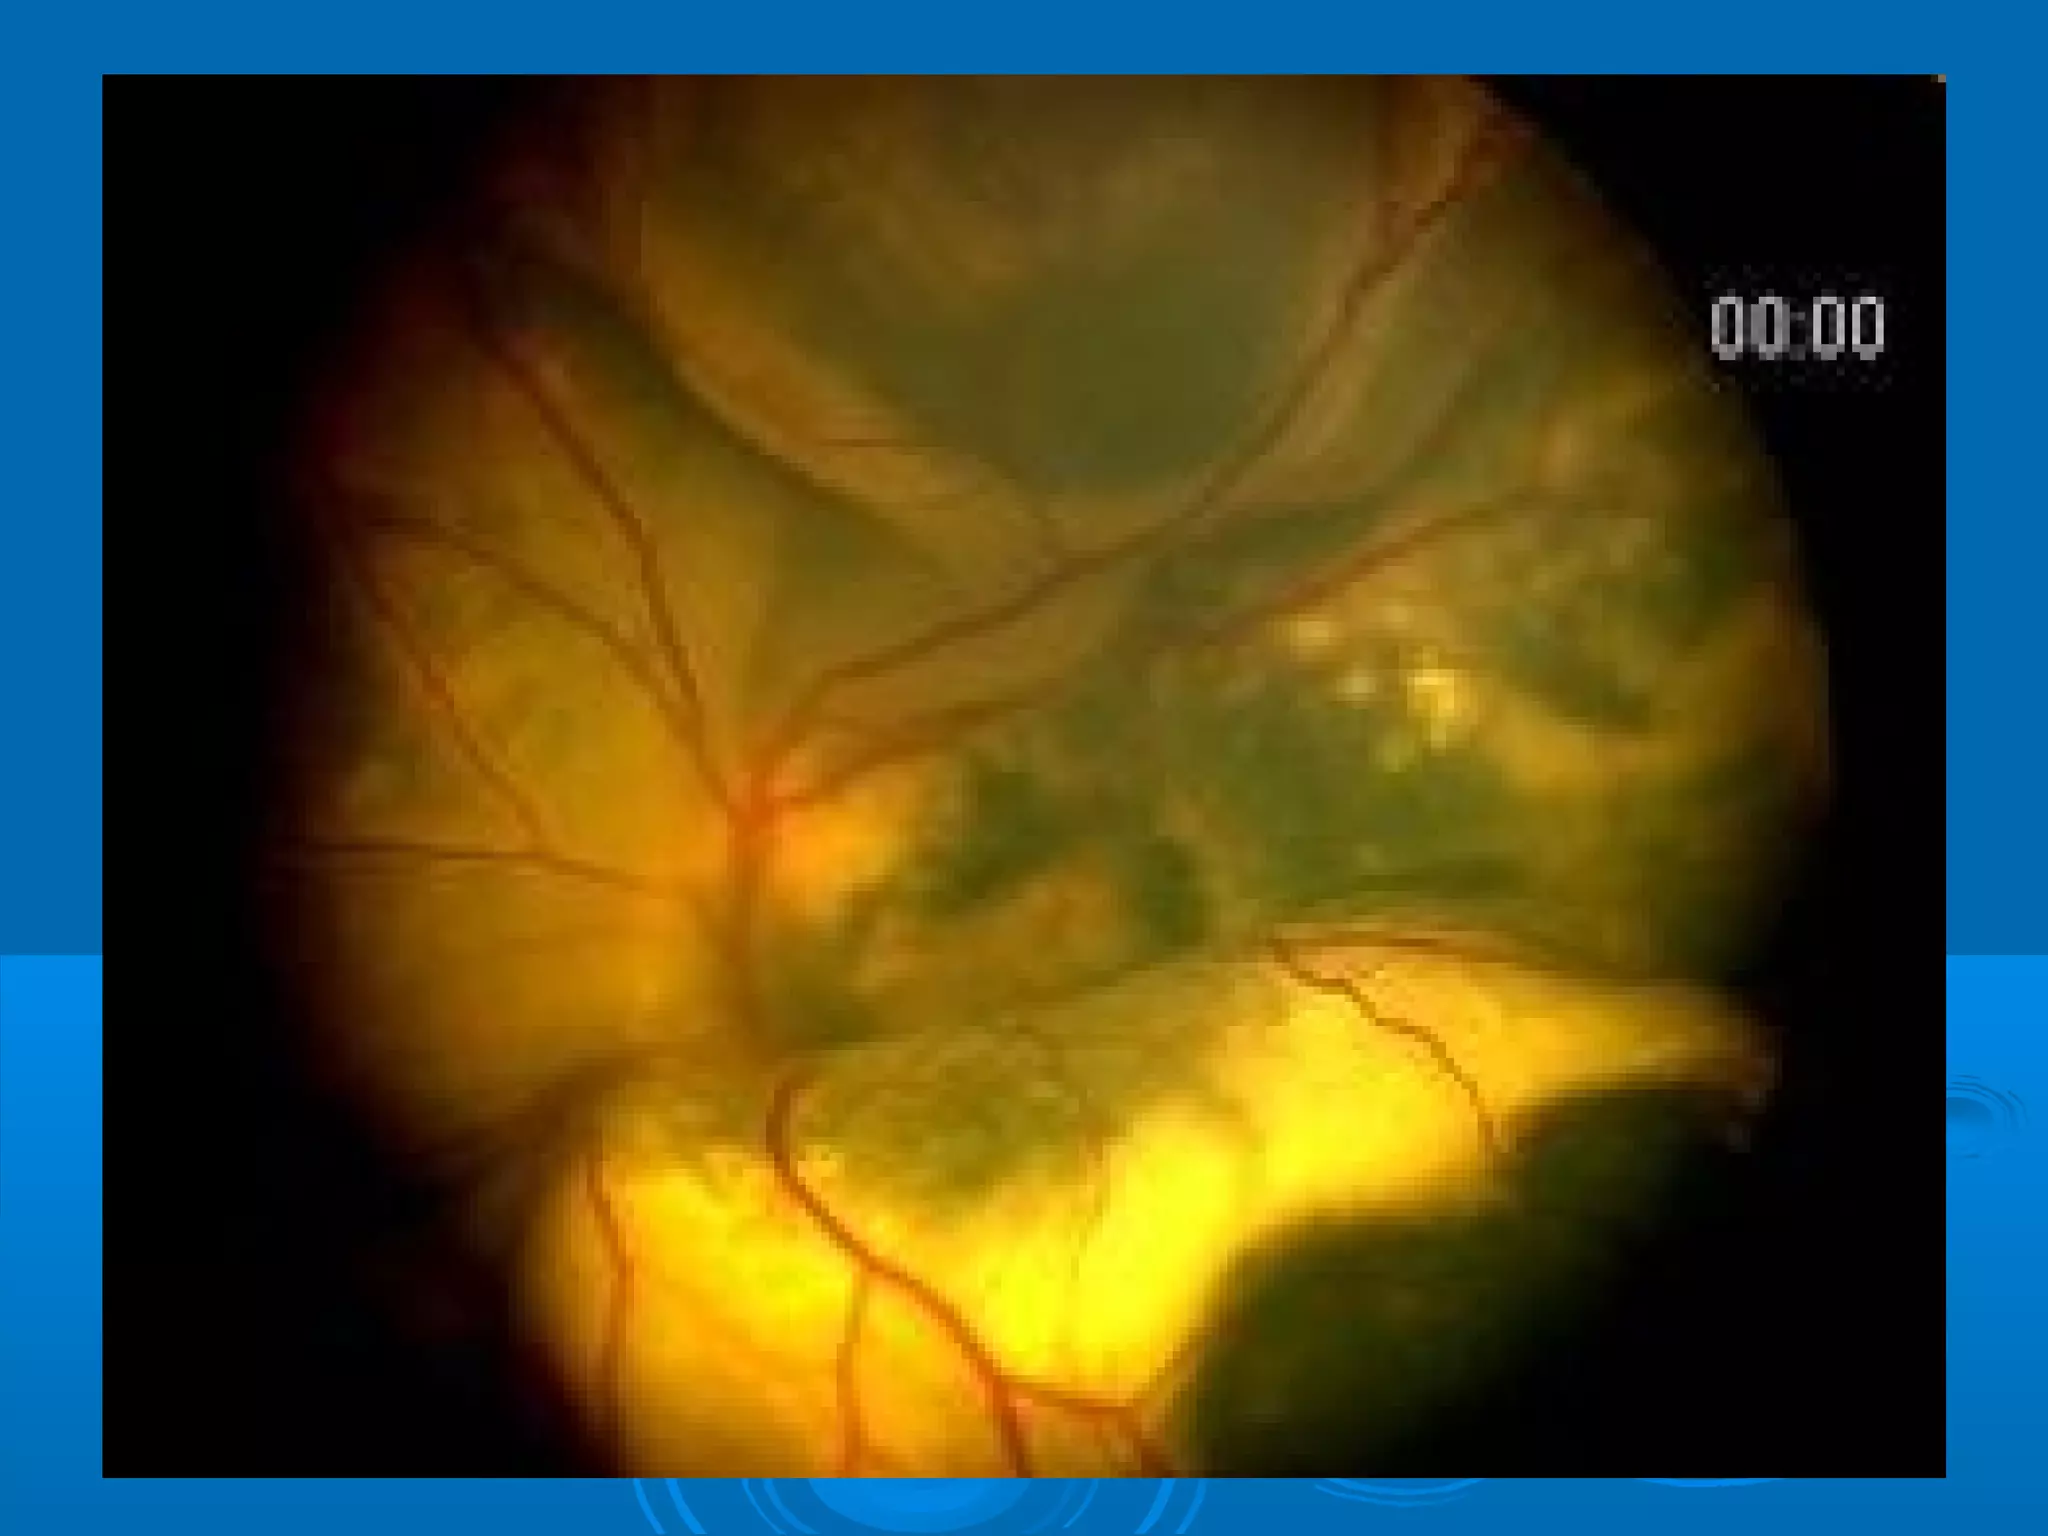

Болезнь Коатса - это идеопатическое заболевание, характеризующееся полиморфными изменениями сосудов сетчатки с массивной экссудацией, чаще всего у детей и подростков, с преобладанием среди мальчиков. Эпидемиология показывает, что заболевание проявляется, как правило, в возрасте 8-16 лет, но возможно его обнаружение и у взрослых. Основные проявления включают ретинальные аномалии, субретинальную экссудацию и постепенно прогрессирующую потерю зрения.